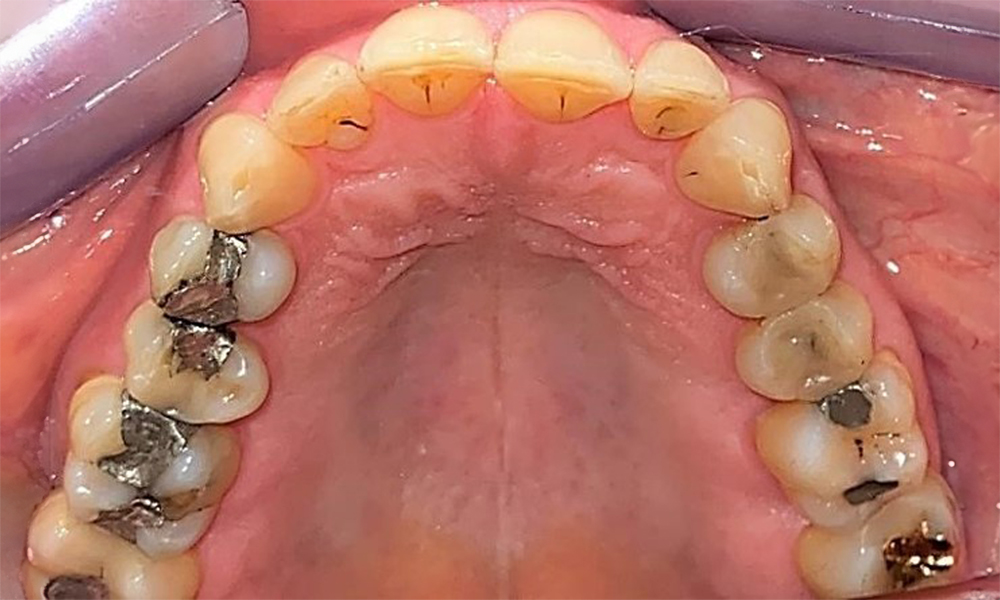

Зъбни резултати

Пациентът има пълно съзъбие с 28 зъба, което включва амалгамни и композитни пломби в областта на моларите и премоларите. На зъб 14 има видима клинична маргинална празнина. Зъб 27 има адекватна златна инкрустация. Налице са и генерализирани атриции и абразии. (фиг. 2, фиг. 3, фиг. 4, фиг. 5, фиг. 6)

Пациентът е с пародонтит II стадий, степен В (5). Клиничните дълбочини на сондиране от 1 до 3 mm са във физиологичния диапазон. Локализирани дълбочини на сондиране от 5 mm са наблюдавани медиопалатинално на 17 и 27. Налице са генерализирани рецесии от 1 до 3 mm с частична загуба на интердентални папили (фиг. 2, фиг. 3, фиг. 4)